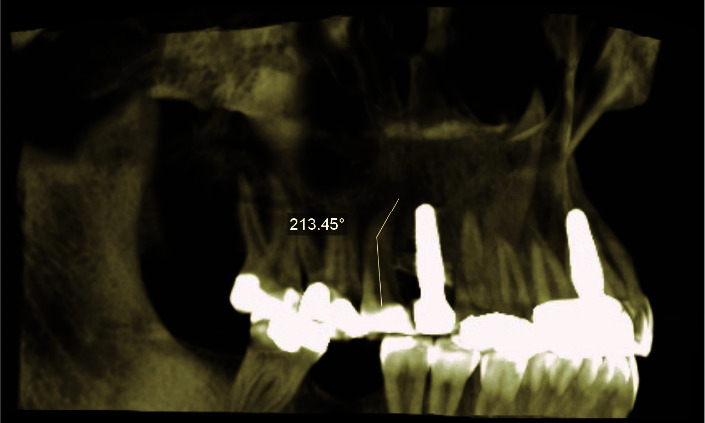

Statement of the problem: As a developmental disorder characterized by an abnormal bend and angle in the longitudinal axis of the tooth root, dilaceration can cause complications in routine dental procedures such as endodontics, orthodontics, and surgical treatments.

Materials and method: This is a retrospective cross-sectional study on 927 premolar teeth and 132 CBCT radiographs of patients obtained from four private radiology clinics in Shiraz (Iran). In this study, the presence, location, direction, and severity of dilaceration in premolar roots as well as its relationship with gender were investigated. Chi-square and Fisher tests were used to analyze the data.

Results: The results showed that 17% of the studied 927 teeth had dilaceration. The prevalence of dilaceration was significantly higher in women than in men (20.3% vs. 13.6%, p= 0.005). The dilaceration rates were significantly higher in the mandibular first and second premolar teeth (31.6% and 26%, p= 0.002) than in the other teeth. In addition, the highest prevalence was in the distal direction with mild severity in the apical third of the root (p< 0.001).

Conclusion: According to the results of this study, the prevalence of dilaceration was relatively high in mandibular premolar teeth especially in women.